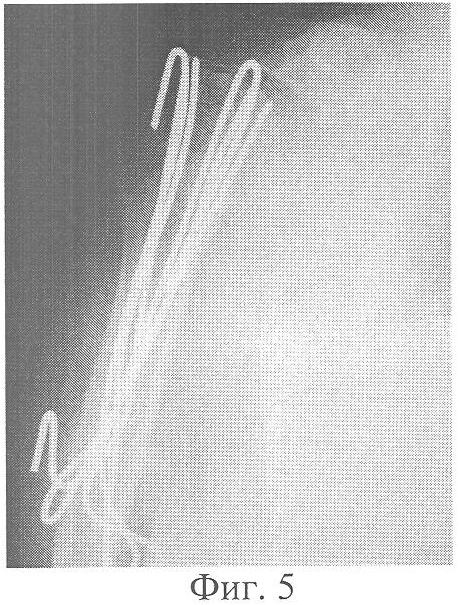

Больная Грачева Л.С., 63 лет, история болезни 1548, госпитализирована на 2-ой день после получения травмы с диагнозом: Оскольчатый перелом хирургической шейки правой плечевой кости с отрывом обоих бугорков со смещением отломков (Фиг.3). Под контролем ЭОП-а произведена закрытая ручная репозиция перелома и остеосинтез напряженными спицами (Фиг.4). На следующий день после операции начата активная лечебная физкультура с движениями в плечевом суставе. В послеоперационном периоде дополнительная внешняя иммобилизация не проводилась. Больная была выписана на 14-ый день после операции на амбулаторное лечение. Через 8 недель после операции на контрольной рентгенограмме выявлено сращение перелома, функция сустава восстановлена полностью. Через 7,5 месяцев после остеосинтеза было произведено удаление напряженных спиц (Фиг.5, 6). Больная функцией конечности довольна, обслуживает себя самостоятельно.

Фиг.5 – рентгенограмма правого плечевого сустава через 7 месяцев после операции. Сросшийся перелом шейки и бугорков плечевой кости.